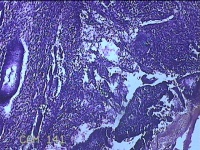

宫腔内容物

性别

女

年龄

43岁

临床诊断

异常子宫出血

一般病史

月经不规则2年余,发现宫颈赘生近1年,宫颈外科可见多个赘生物。

标本名称

大体所见

纱布一块,内有灰白暗红色不规则碎组织1.8x1.3x0.3cm一堆。